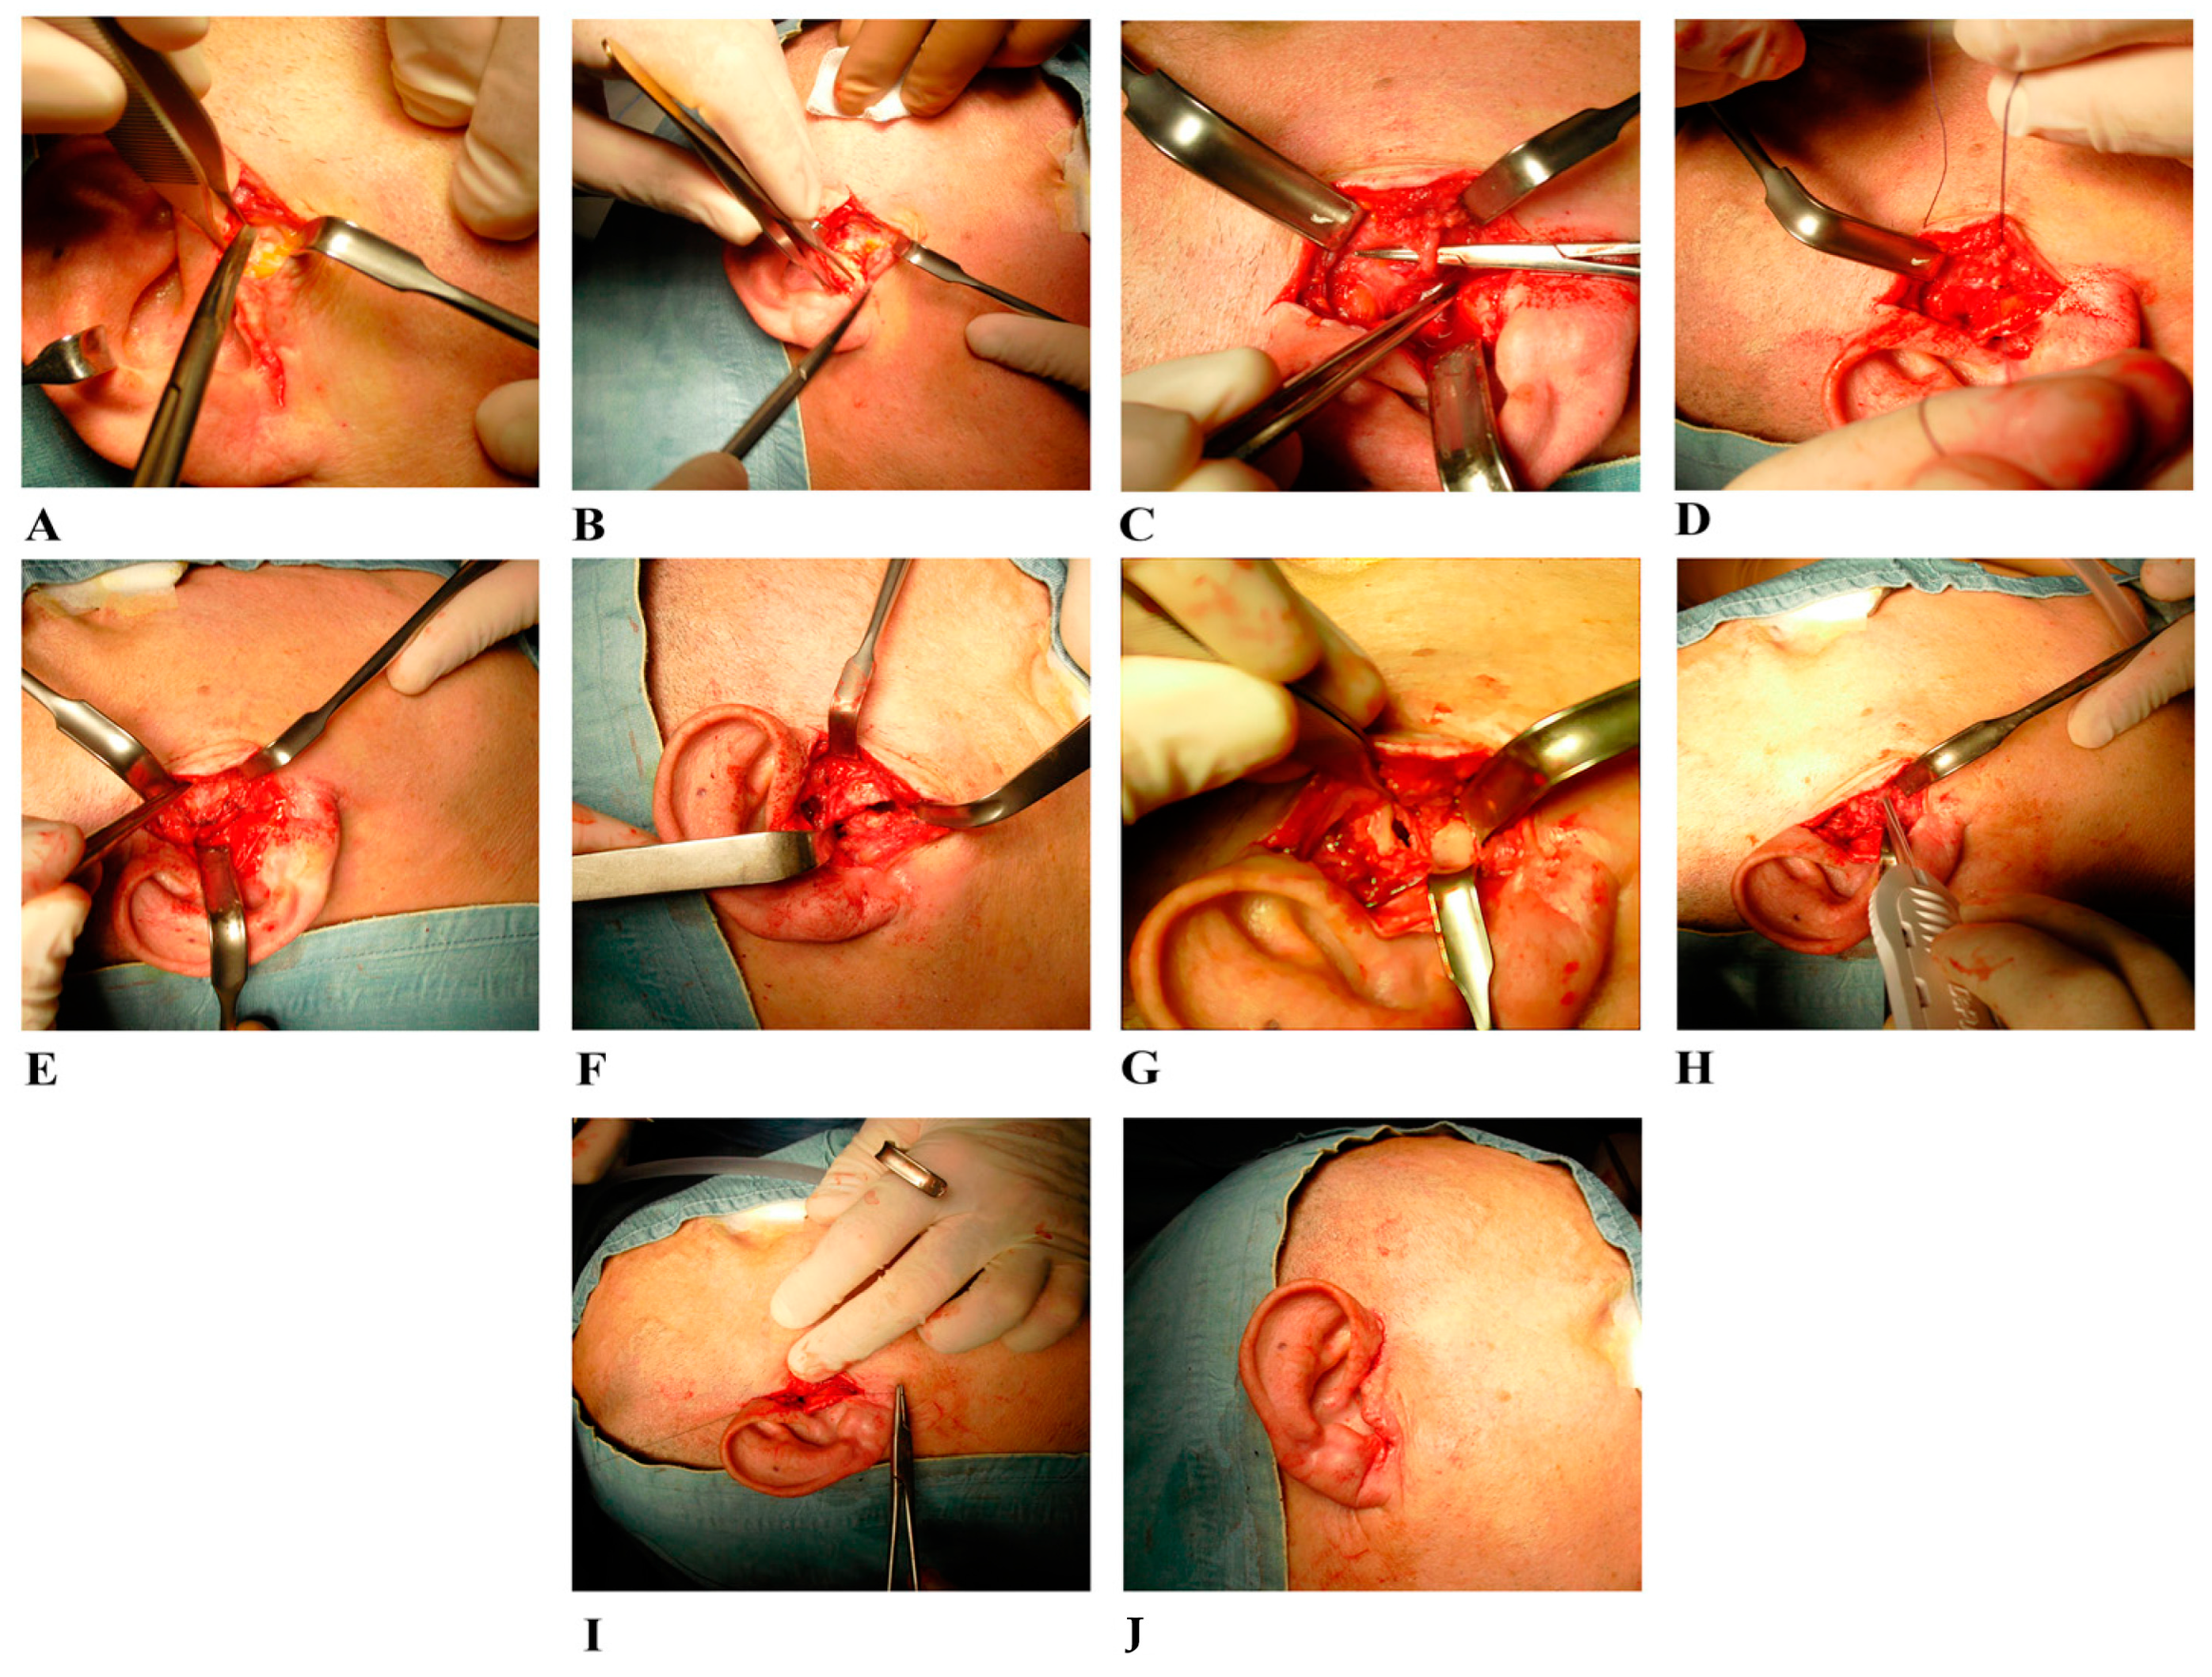

2.2. Surgical Treatment

2.3. Samples Collection